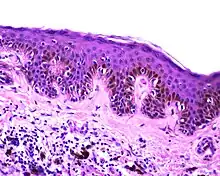

Lentiginous melanocytic naevus | |

Melanocytic nevi can mainly be classified by depth, being congenital versus acquired, and/or specific dermatoscopy or histopathology patterns:

Junctional nevus | Along the junction of the epidermis and the underlying dermis.[15] | May be colored and slightly raised.[16] | ![]() |